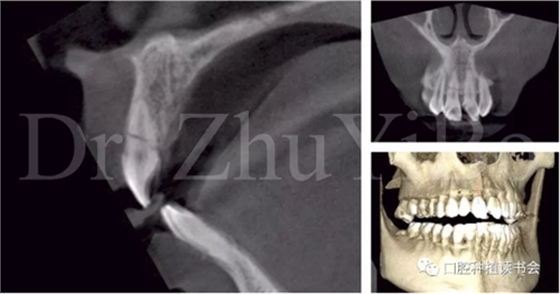

臨床檢查發(fā)現(xiàn):右上中切牙冠根折,斷面位于齦緣下4到5個(gè)毫米。左上中切牙及右上側(cè)切牙,切角缺損,牙髓活力正常(圖7)。

術(shù)前cbct顯示:右上中切牙牙根牙槽突類型為一型(圖8)。牙齦為厚型牙齦類型;咬合關(guān)系基本正常。

圖7 外傷導(dǎo)致11冠根折

圖8 CBCT:11可見明顯根折線,無法保留